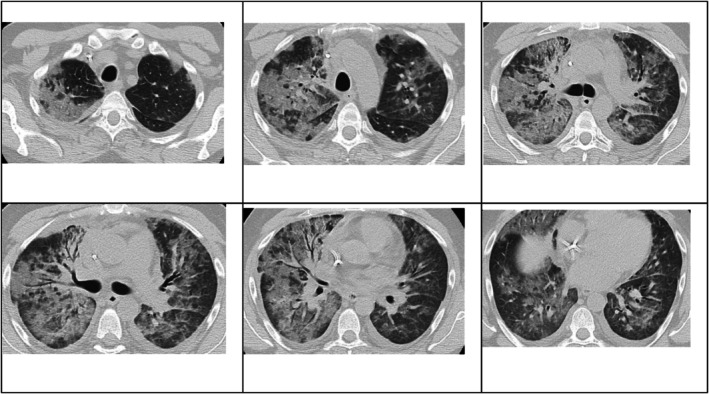

移植后综合征(PES)是自体造血干细胞移植(AHSCT)的一种重要且可能危及生命的并发症,表现为发热、皮疹和肺部受累。尽管具有临床意义,PES仍然是一个诊断挑战,经常被误认为是一种感染过程,导致适当治疗的延误。我们报告一例38岁男性复发霍奇金淋巴瘤和葡萄糖-6-磷酸脱氢酶(G6PD)缺乏症患者在AHSCT后发展为严重的PES。患者经历了严重的呼吸窘迫和精神状态的改变,需要插管和重症监护病房住院。尽管使用了广谱抗菌药物,他的病情仍在恶化,直到静脉注射皮质类固醇,随后出现了显著的临床反应。本病例强调了早期识别和适当管理PES的重要性。

Post-engraftment syndrome (PES) is a significant and potentially life-threatening complication of autologous haematopoietic stem cell transplantation (AHSCT) that presents with fever, skin rash and pulmonary involvement. Despite its clinical relevance, PES remains a diagnostic challenge and is often misidentified as an infectious process, leading to a delay in the appropriate treatment. We report the case of a 38-year-old man with relapsed Hodgkin's lymphoma and glucose-6-phosphate dehydrogenase (G6PD) deficiency who developed severe PES following AHSCT. The patient experienced severe respiratory distress and an altered mental status, necessitating intubation and intensive care unit admission. Despite broad-spectrum antimicrobial coverage, his condition deteriorated until intravenous corticosteroids were administered, with a subsequent remarkable clinical response. This case highlights the importance of the early recognition and appropriate management of PES.